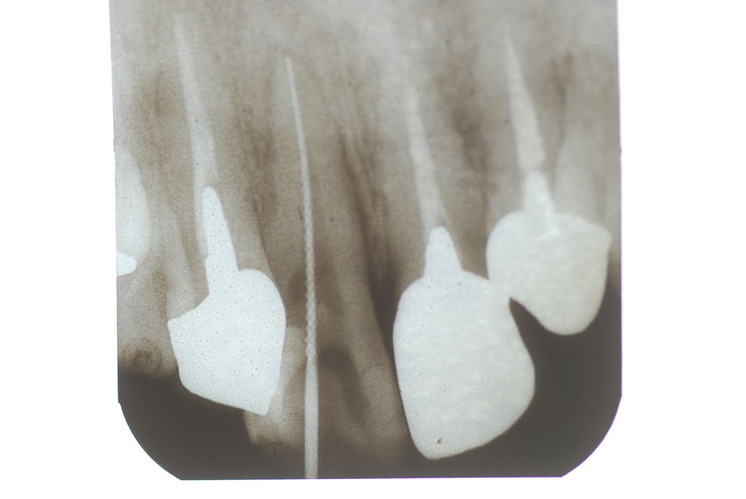

歯周病の疑いで東京のかなり遠方の方が来院されました。

驚くべきことですが、定期検診は受けていたそうです。しかしながら歯周病の指摘は受けたことがないそうです。

何故か?定期検診が虫歯のチェックのみになり、又肝心の歯周病の検査や歯周病の部分の予防や治療のためのブラシの使い方などを学んだ事がないのです。

本当に患者さんのことを考えると憂鬱になります。歯周病が悪化すると殆ど回復は無理だからです。